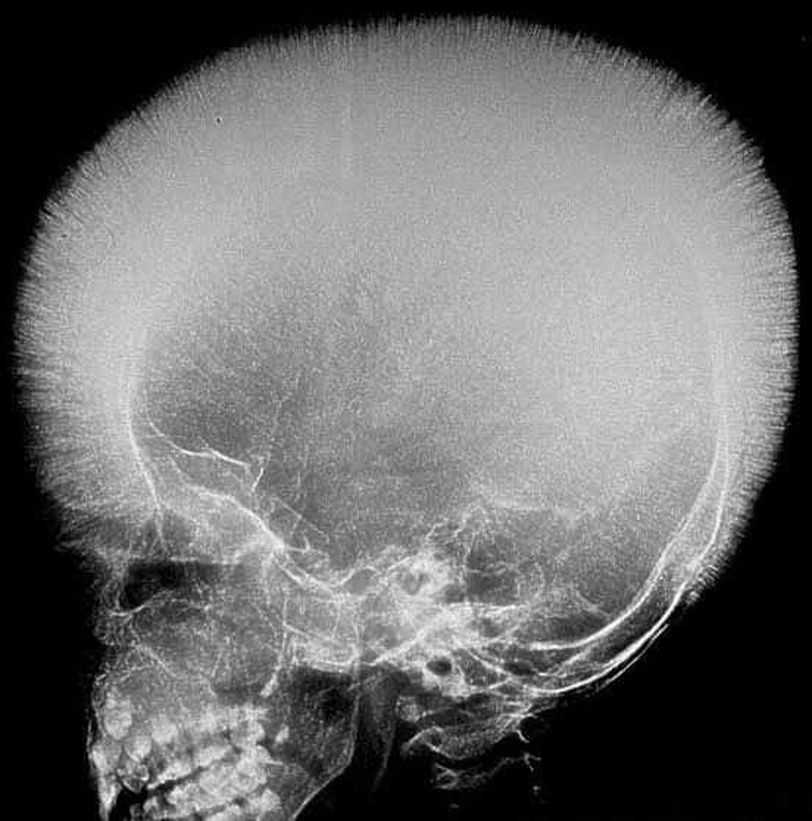

This X-ray shows Hair on end appearance and it can be found in patient with : A-Iron deficiency anemia B-Thalassaemia C-sickle cell anemia D-Megaloblastic anemia

B,and C

The Correct answer is B&C